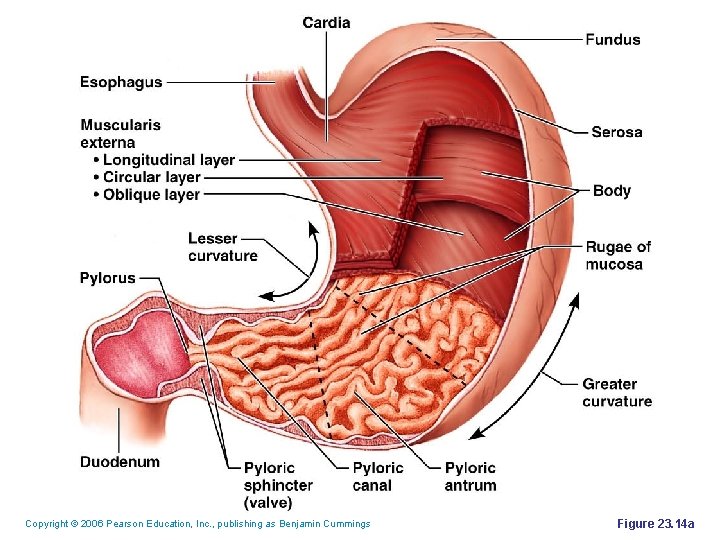

Copyright © 2006 Pearson Education, Inc. , publishing as Benjamin Cummings Figure 23. 14 a

Digestion in the Stomach § The stomach: § Holds ingested food § Degrades this food both physically and chemically § Delivers chyme to the small intestine § Enzymatically digests proteins with pepsin Copyright © 2006 Pearson Education, Inc. , publishing as Benjamin Cummings